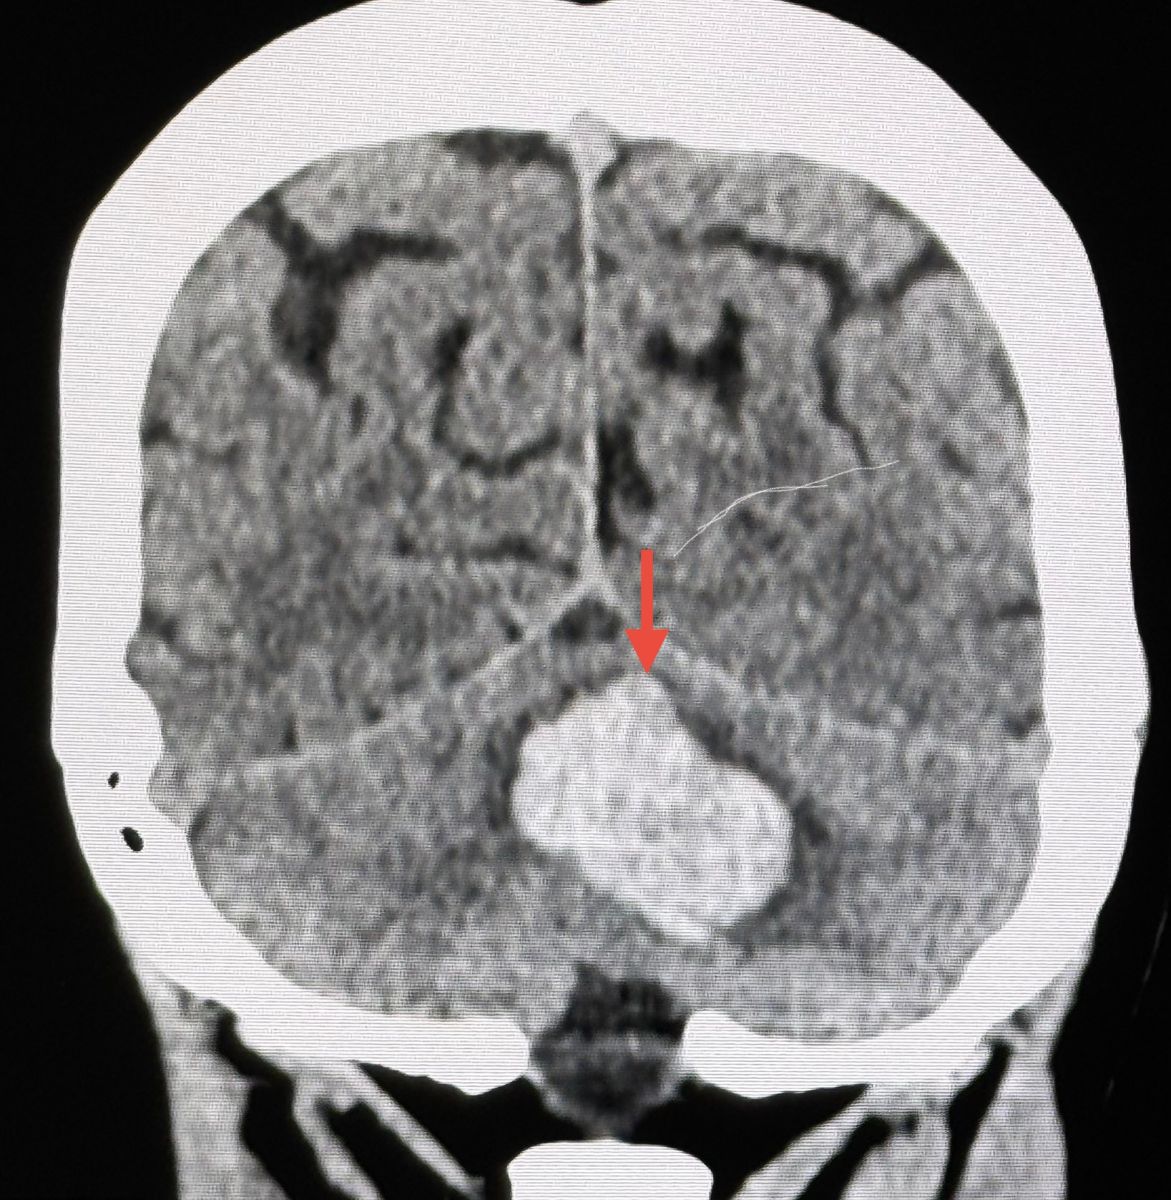

พบมีเลือดออกขนาด 3.5 × 4.5 × 3.2 เซนติเมตร ในสมองส่วน cerebellum หรือสมองน้อยซึ่งเป็นส่วนหนึ่งของสมองที่อยู่บริเวณท้ายทอย ยังไม่มีภาวะโพรงสมองคั่งน้ำ ตรวจเลือดการทำงานของไตปกติ วัดระดับฮอร์โมน metanephrine และ normetanephrine ในเลือดปกติ อัลตราซาวด์ไม่พบเนื้องอกต่อมหมวกไต ไม่พบโรค Pheochromocytoma

วินิจฉัย : ภาวะเลือดออกในสมองน้อยเฉียบพลัน (Acute intracerebellar hemorrhage) จากหลอดเลือดในสมองแตกเนื่องจากความดันโลหิตสูงมาก ทำให้มีเลือดออกในเนื้อสมองอย่างเฉียบพลัน ภาวะนี้เป็นภาวะฉุกเฉินรุนแรง และอาจนำไปสู่ความพิการหรือเสียชีวิตได้ ให้ยาลดความดันทางหลอดเลือดทันที ให้ยาฉีด mannitol ลดความดันในกระโหลกศีรษะจากภาวะสมองบวม ปรึกษาศัลยแพทย์ประสาทแนะนำไม่ต้องผ่าตัด ติดตามอาการใกล้ชิดในไอซียู คนไข้ดีขึ้นช้าๆ พูดชัดขึ้น ความดันควบคุมได้ดี เปลี่ยนเป็นยากิน ทำคอมพิวเตอร์สมองซ้ำ 3 วันต่อมา เลือดไม่ออกเพิ่มขึ้นที่ cerebellum ย้ายออกจากห้องไอซียูได้ ให้ยาลดความดันชนิดกินต่อไป การทรงตัวดีขึ้น ยังเดินเซๆ พูดชัดแล้ว ไม่ปวดศีรษะ ทำกายภาพฝึกเดินต่อไป ทำคอมพิวเตอร์สมองซ้ำ 2 สัปดาห์ต่อมา พบบริเวณที่เลือดออกในสมองน้อย cerebellum ลดลงมาก คุมความดันได้ดี 120/80 กลับบ้านได้ 16 วันหลังเข้ารักษาใน รพ.